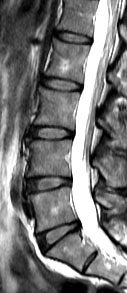

The current study was a cross-sectional assessment of adults from this cohort who were 21 years of age and older. A total of 2,599 individuals were assessed with magnetic resonance imaging (MRI). Amongst them, 27% (n=709) did not have disc degeneration while 73% (n=1,890) had. Of the subjects who have disc degeneration, 7% were underweight, 48% were in the normal weight range, 36% were overweight, and 9% were obese. Overweight and obese individuals were also found to have a greater extent and severity of disc degeneration in comparison to those individuals of normal weight or underweight.